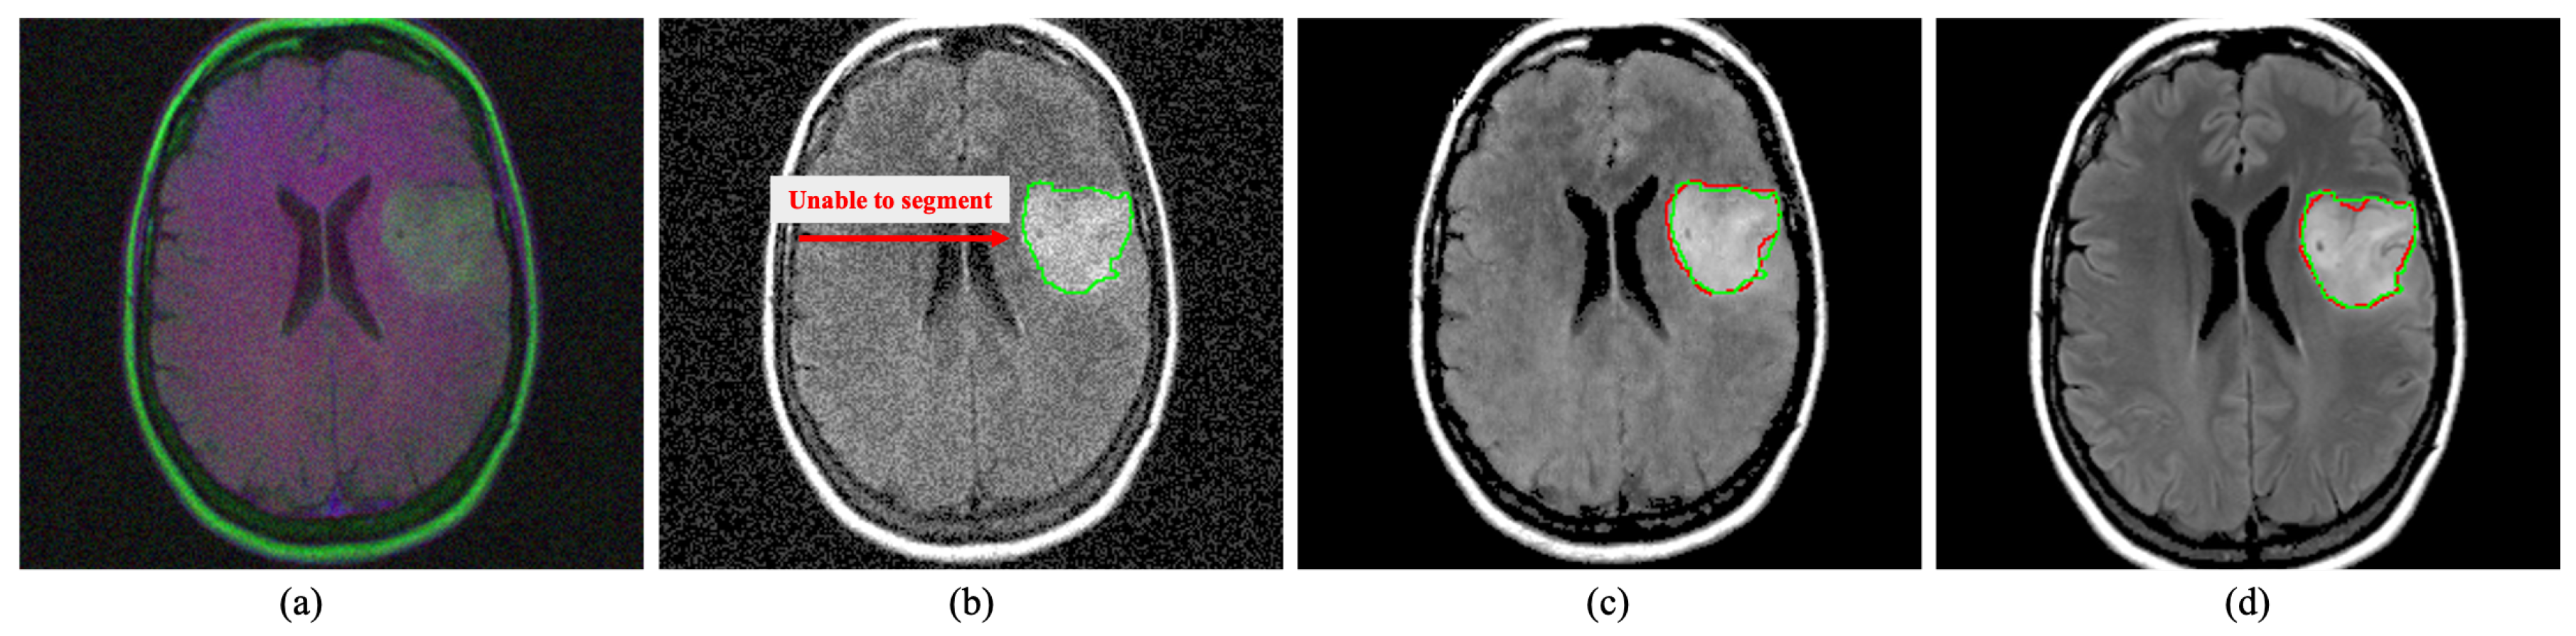

4.3.2. Medical Image Segmentation

The image noise can also startlingly effect the medical image segmentation process similar to the detection methods, as shown in Figure 10. Here, segmentation has performed on brain MRIs using well-known U-Net architecture [68]. It has observed that image noise make the segmentation process substantially unsatisfactory. However, a sophisticated MID method like the proposed DRAN can assist the segmentation method by mitigating image noise.

Figure 10. Segmentation on brain MRI image. The green and red outline indicate the ground truth and the segmented area. The proposed DRAN can drastically improve the segmentation performance by excluding the noise present in the target image. (a) Noisy image. (b) Noisy image + U-Net [68]. (c) Denoised image obtained with DRAN + U-Net [68]. (d) Reference clean image + U-Net [68]. Source by: (https://www.kaggle.com/mateuszbuda/lgg-mri-segmentation).